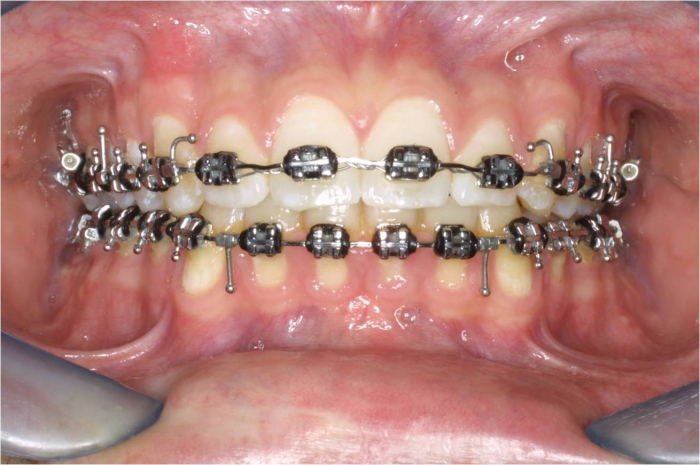

Mordida inicial